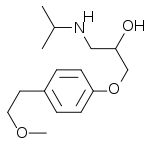

Propanolamines are a class of chemical compounds, many of which are pharmaceutical drugs. They are amino alcohols that are derivatives of 1-amino-2-propanol.[1]

Propanolamines include: